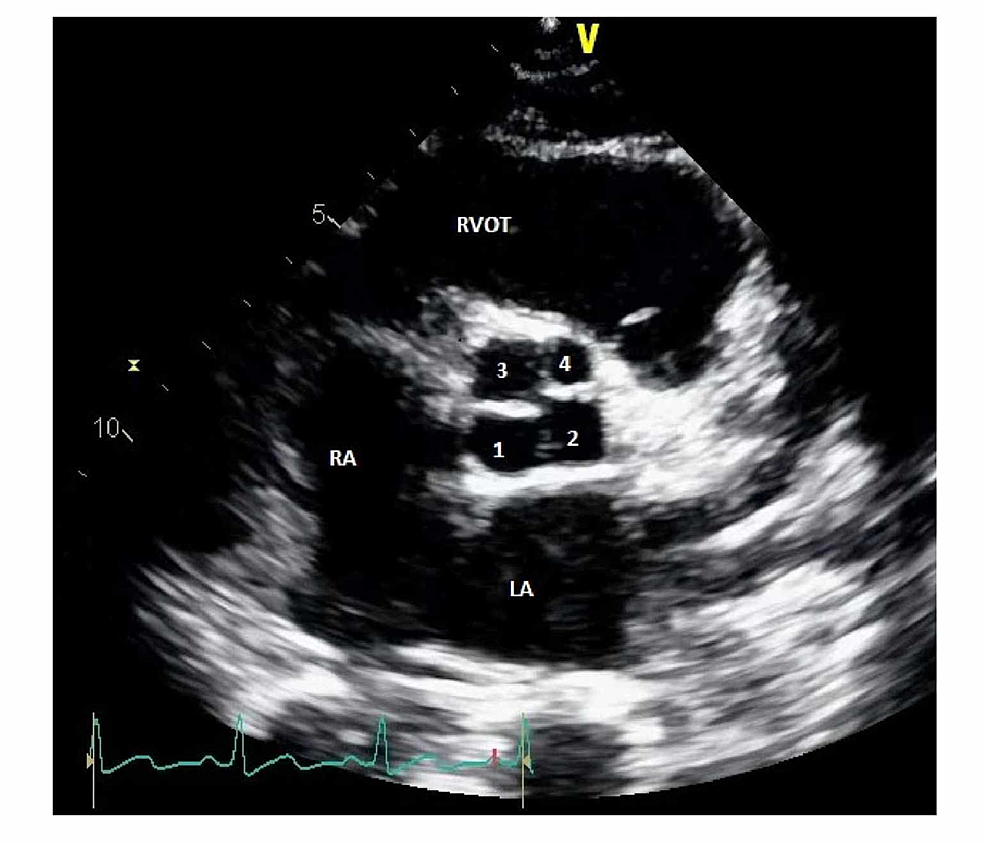

Aortic Flow Reversal

o Pulsed-wave Doppler of the proximal descending aorta in the suprasternal notch view examining for retrograde flow

▪ Retrograde flow indicates moderate to severe aortic regurgitation

o Pulsed-wave Doppler of the descending aorta in the subcostal view examining for retrograde flow

▪ Retrograde flow indicates severe aortic regurgitation

o Velocity greater than 0.6 m/s, VTI greater than 15 cm, or end-diastolic velocity greater than 20 cm/s may indicate significant aortic regurgitation